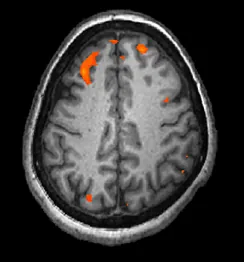

Obraz pokazuje tkankę mózgową w kolorze szarym, ale niektóre, niewielkie obszary świecą na czerwono.

Ilustracja 3.28 fMRI pokazuje zmiany aktywności mózgu w czasie. Rysunek przedstawia pojedynczą klatkę zarejestrowaną w czasie badania. (Źródło: modyfikacja pracy Kim J., Matthews N.L., Park S.).